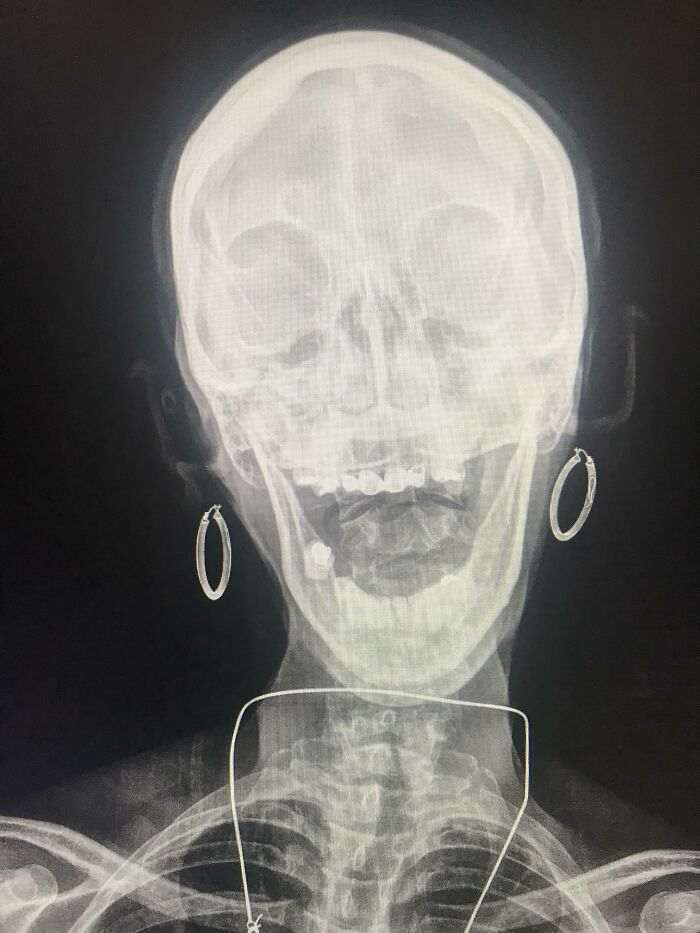

Улыбочку!